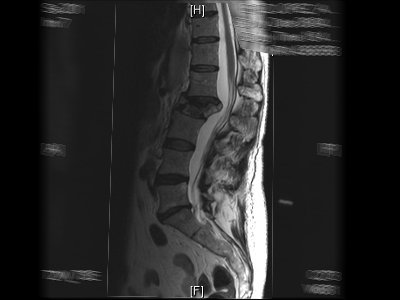

Tumores vertebrales y hernia lumbar